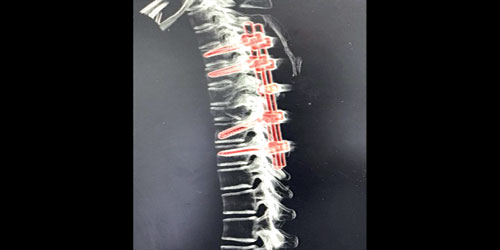

وكان المصاب قد حضر إلى طوارئ المستشفى إثر تعرضه لحادث مروري, أدى لحدوث إصابات متعددة مع نزيف داخل التجويف الصدري من الجهتين, تسبب في هبوط حاد في الدورة الدموية مع وجود كسر وخلع في العمود الفقري, على مستوى الفقرتين الظهريتين السادسة والسابعة, مع وجود قطع كامل للحبل الشوكي.

وقام الفريق بإجراءات طبية ساهمت في استقرار الحالة العامة للمريض, ومن ثم تم إجراء عمل جراحي ناجح بفضل الله, تضمن إعادة تثبيت العمود الفقري للمريض بواسطة أطباء جراحة المخ والأعصاب.